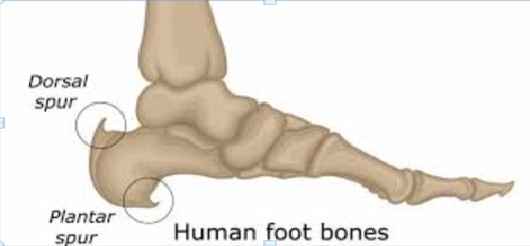

Heel spurs are calcium deposits that cause a bony protrusion on the underside of the heel bone. Often associated with plantar fasciitis, heel spurs develop over time due to strain on foot muscles and ligaments, repeated tearing of the membrane covering the heel bone, or prolonged stress from walking or running. While some people with heel spurs experience no discomfort, others suffer from sharp pain in the heel, especially during standing or walking. Diagnosis is typically confirmed through X-rays. Conservative treatments include rest, stretching exercises, anti-inflammatory medications, and orthotic inserts. Wearing supportive shoes can also help relieve pressure on the heel. Surgery is considered only in severe, chronic cases when other treatments have failed to provide relief.